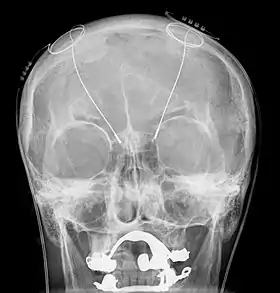

تحریک عمقی مغز (به انگلیسی: Deep brain Stimulation) نوعی روش درمانی (جراحی) در پزشکی است که در طی آن الکترودهایی در داخل مغز بیمار قرار داده میشوند. این الکترودها پس از کاشته شدن در مغز به یک دستگاه مولد پالس الکتریکی (به انگلیسی: Pulse Generator) متصل میشوند.[1][2] پالس الکتریکی تولید شده توسط دستگاه پالس ژنراتور از طریق الکترودهای کاشته شده در مغز به بافتهای عمقی مغز انتقال یافته و از این طریق اثر درمانی خود را اعمال مینماید. روش درمانی تحریک عمقی مغز برای اولین بار در انسان در سال ۱۹۸۷ توسط جراح مغز و اعصاب فرانسوی علیم-لویی بن عبید (Alim-Louis Benabid) به کار گرفته شد. در حال حاضر از این روش درمانی جهت معالجه بیمار پارکینسون و تعدادی از بیماریهای عصبی و روانی استفاده میگردد.[3]

سیستم DBS سه بخش دارد که درون بدن نصب می شوند:

- تحریک کننده عصبی. دستگاهی ضربان ساز و قابل برنامه ریزی است که با باتری کار میکند و باعث تولید پالس های الکتریکی می شود. این دستگاه زیر پوست قفسه سینه یا شکم قرار میگیرد.

- لید. یک سیم با تعدادی الکترود در نوک آن است که پالس های الکتریکی را به بافت مغزی منتقل می کند. الکترود ها درون مغز قرار میگیرند و از یک سوراخ کوچک در جمجمه به سیم ها متصل شده اند.

- سیم های انتقال جریان. سیم هادی که لید ها را به تحریک کننده متصل میکنند. این سیم معمولاً در زیر پوست جایگذاری میشود و از جمجمه به پشت گوش و گردن و نهایتا به سینه میرسد.[4]